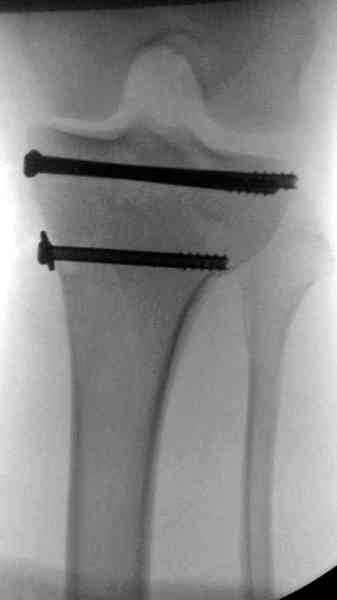

Предыдущей сменой до 4:00 утра по поводу открытого перелома бедра, тибиал плато, пилон и надколенника сделана операция.

Пострадавшему 21 г., травма скоростная, после I&D с расширением раны, на бедре сделана операция ретроградным интрамедуллярным штифтом, остеосинтез с частичной резекцией надколенника и ушивание собственной связки.

На голень наружный фиксатор, рану на бедре ушили (рана была изнутри кнаружи всего 2 см). По протоколу травматических больных, до операции обследован ангиографически, (у больного дистально не смогли определить пульсацию) сосудистый хирург подтвердил проходимость на всем протяжении магистрального сосуда нижней конечности по снимкам ангиограмм.